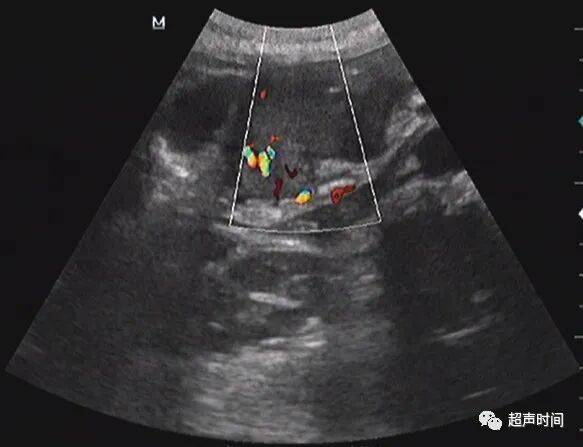

胃窦壁不规则增厚,回声减低, CDFI :其内可见高阻血流。胃窦壁僵直,探头按压长时间不蠕动。余胃壁蠕动良好。

图 6 CDFI : 增厚的胃窦壁内可见粗大的高阻血流